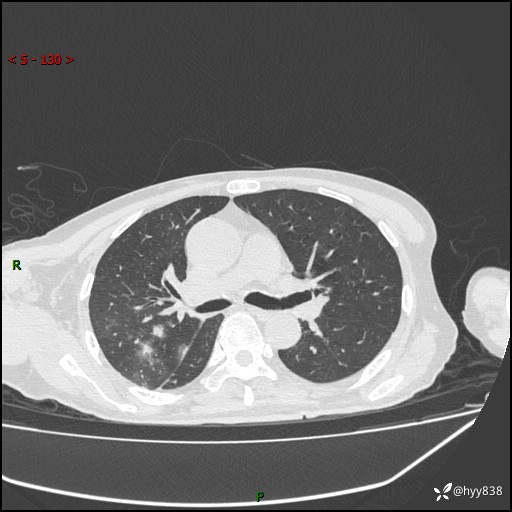

一个月后第二次CT检查(常规抗感染,患者不配合:增强、住院---)